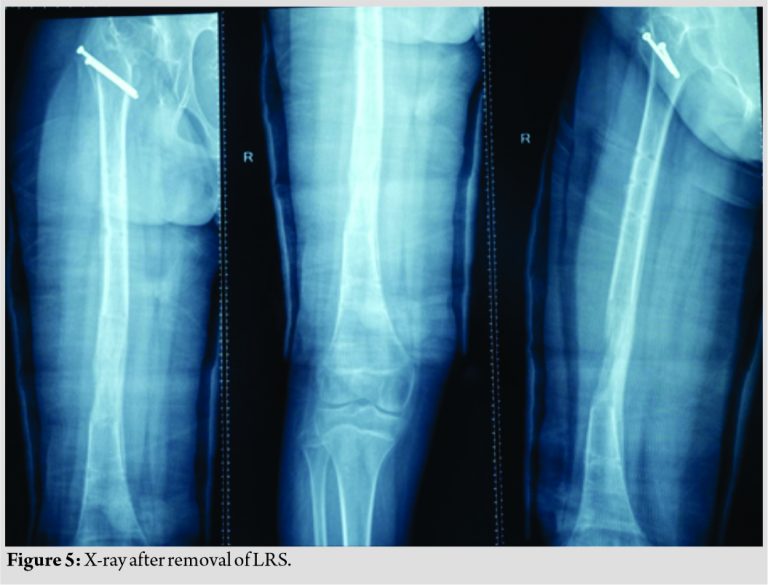

Careful follow-up evaluation was done and distraction was stopped once limb length equalization was achieved (Fig. 4-6). The fixator was removed after 112 days. The patient had no complication postoperatively except mild pain during early phases of distraction which was managed with high-dose analgesics and knee stiffness in the later part of the distraction. She achieved a complete range of motion of knee with extensive physiotherapy and quadriceps strengthening exercises. At final follow-up of 6 months, the patient had no equinus at the ankle with improvement in hip abduction with minimal abductor lurch.